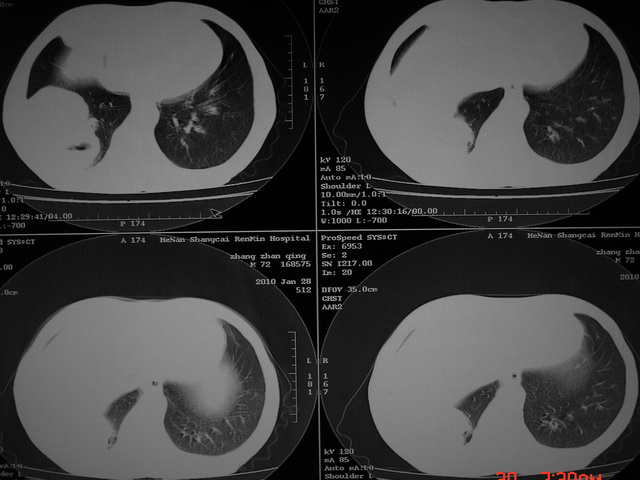

xx m 72岁农民 右侧胸痛6月余,咳嗽,无发热、咯血等

右下周围型肺癌,并右肺门、纵膈淋巴结、内乳淋巴结转移,右胸膜转移累及前胸壁。鉴别:脓肿、tb、淋巴瘤。病理类型可能为大细胞型。

这个病人有点复杂了,上纵隔像是占位,右肺下叶见壁光整厚壁空洞加液平,像是肺脓肿,中叶病灶牵涉到胸膜及胸壁,形态看像是炎性病变,总之不能除外恶性病变,还是穿刺或增强后再说。

右下周围型肺癌。偏心空洞形成伴感染。

右下周围型肺癌伴转移